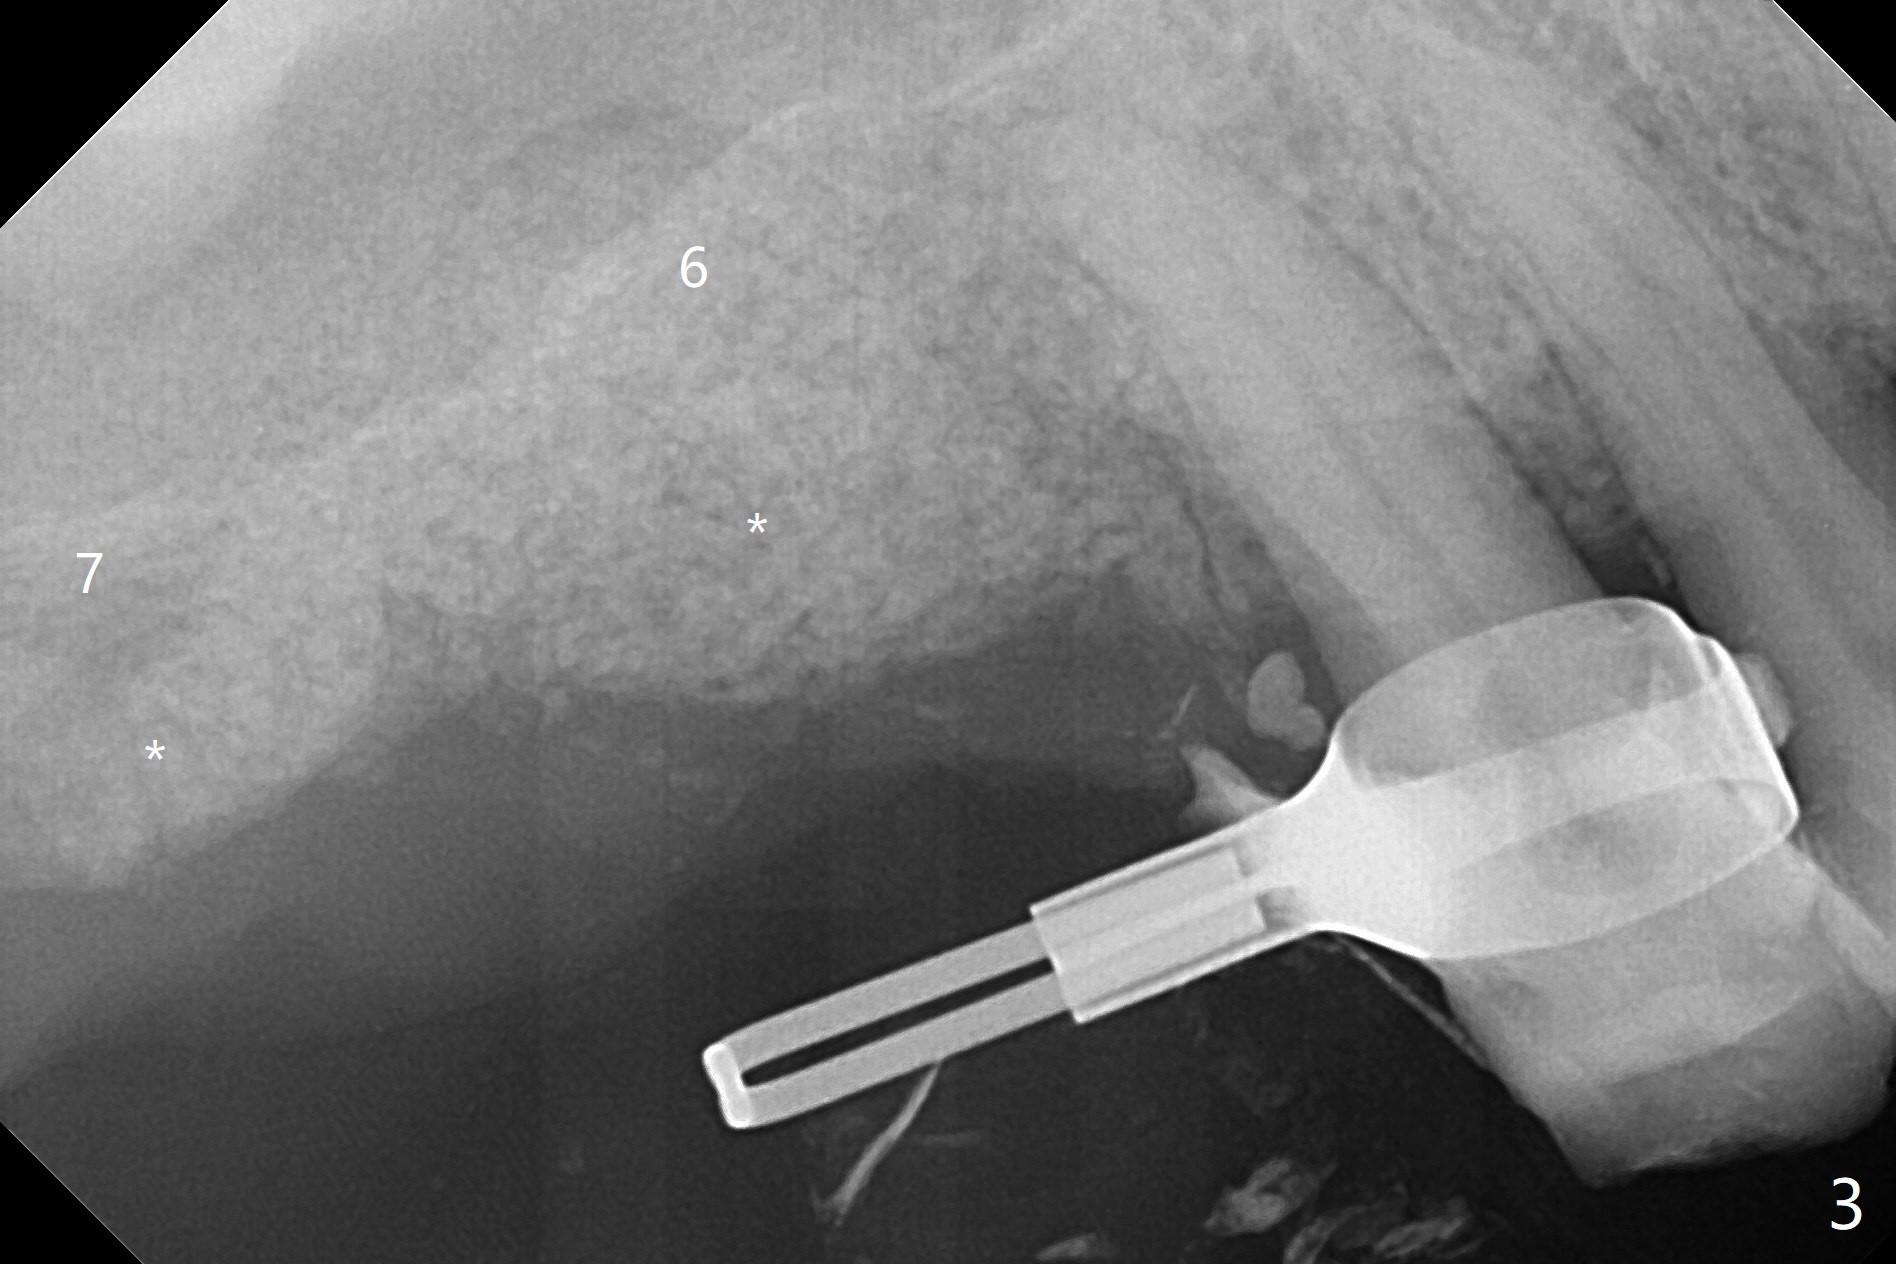

69岁男2.5年前CT显示右上7根尖骨质很薄(图一:*),大约一年后拔除,没植骨。上周拔除8时,发现6腭侧牙周袋出脓(图二:<)。拔除后者清创后,往远中牙龈下分离7位点,然后6,7植骨(图三:*),7骨质高度增加一倍(植骨后近7毫米)。覆盖两片PRF膜,近中放置小块胶原塞(牙槽嵴高),4-0 PGA缝合,置放间隙保持器(放置攀(loop),增加固位)和牙周敷料。术后13天敷料保持原位,卫生也好(图四),病人明天到外地几个月,交代他两周后撤除敷料。没有不便,不必去掉保持器。